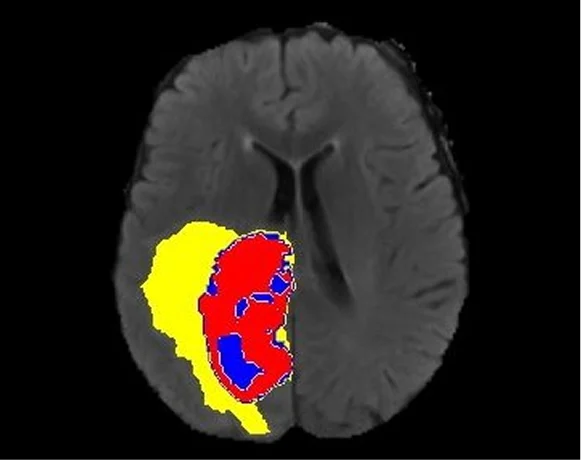

Pareidolia’s annotation of medical images spans diverse pathologies — from coronary artery calcification and obstructive hydrocephalus to complex multi-organ segmentation tasks — precisely to ensure this clinical breadth in every dataset delivered.

Consider the segmentation of a pulmonary nodule on a chest CT. The boundary between the nodule and the adjacent parenchyma is not geometrically obvious. Is the ground-glass component included? How is pleural attachment handled? What constitutes the margin of a spiculated lesion? A fellowship-trained thoracic radiologist brings subspecialty knowledge to these decisions that a generic image labeller cannot replicate.

Poorly annotated data propagates labelling errors through model training. Models trained on noisy ground truth learn to replicate annotation errors at scale and may still achieve acceptable benchmark accuracy on similarly noisily labelled test sets, making the problem invisible until clinical deployment exposes it. This is precisely why radiologist-led quality assurance, multi-stage quality review, and clinically informed annotation practices are not optional premium features. They are the foundation of trustworthy medical AI.

Pixel-accurate segmentation across CT, MRI, PET, ultrasound, X-ray, and digital pathology. Domain-driven annotation workflows covering organ, lesion, vessel, and disease pathology segmentation with multi-layered quality assurance in medical imaging. AI-ready output formats suitable for all major machine learning frameworks.

Comprehensive medical image labeling services — bounding boxes, polygons, keypoints, semantic masks, measurement tasks, and complex multi-class annotations. Expert annotation spanning coronary artery calcification, obstructive hydrocephalus, and hundreds of other disease patterns. Multi-modal support across X-ray, CT, MRI, ultrasound, and digital pathology.